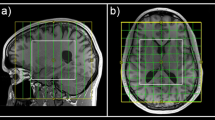

Participants underwent a 1H-MRS scan in a 3 Tesla General Electric MR750 Discovery scanner using a 32-channel head coil. A T1-weighted high resolution sagittal ADNI Go Spoiled Gradient Recalled (SPGR) anatomical with repetition time (TR) = 7.312 ms, echo time (TE) = 3.016 ms, inversion time (TI) = 400 ms, flip angle (FA) 11°, field of view 270 mm, 256 ×256 matrix, 196 slices, voxel dimensions: 1.055 ×1.055 ×1.2 mm was used for spectroscopy voxel positioning and further voxel tissue segmentation. A single-voxel (35 ×30 ×25 mm) was positioned to include the left striatum region of interest (ROI) using the anatomical scan (see Supplementary Fig. 1) and a Mescher-Garwood Point-Resolved Spectroscopy (MEGA-PRESS) [49] sequence (TR = 2000 ms, TE = 68 ms, bandwidth = 5 kHz; number of data points = 4096; 320 averages (160 ON and 160 OFF); phase cycle length of two; FA 90° (excitation pulses); CHESS water suppression) was used to quantify GABA+ (i.e. GABA + macromolecules) and glutamate. Additionally, 16 unsuppressed water scans were acquired for further water scaled metabolite quantification.

The 1H-MRS voxel was coregistered to the SPGR anatomical scan (see Supplementary Fig. 1) using the standalone coregistration routine from Gannet 3.0 (http://www.gabamrs.com) running in MATLAB 9.2.0 (The Mathworks Inc., Natick, Massachusetts, USA) which then runs the Statistical Parametric Mapping 12 (SPM12) (https://www.fil.ion.ucl.ac.uk/spm/software/spm12) segmentation tool to extract the proportion of gray matter (pGM), white matter (pWM) and cerebrospinal fluid (pCSF) within the voxel (see Supplementary Fig 3). These tissue proportion values were then used to correct the water-scaled metabolite values for partial volume effects and different amounts of ‘visible’ water in each tissue type. Each individual metabolite was corrected using the following calculation: